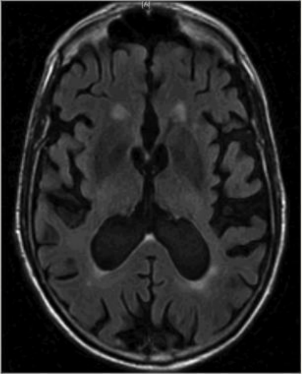

Q

What is this?

A

Communicating hydrocephalus at the level of lateral ventricle

Where is the blockage in a communicating hydrocephalus?

After it exits ventricles, most commonly at level of arachnoid villi